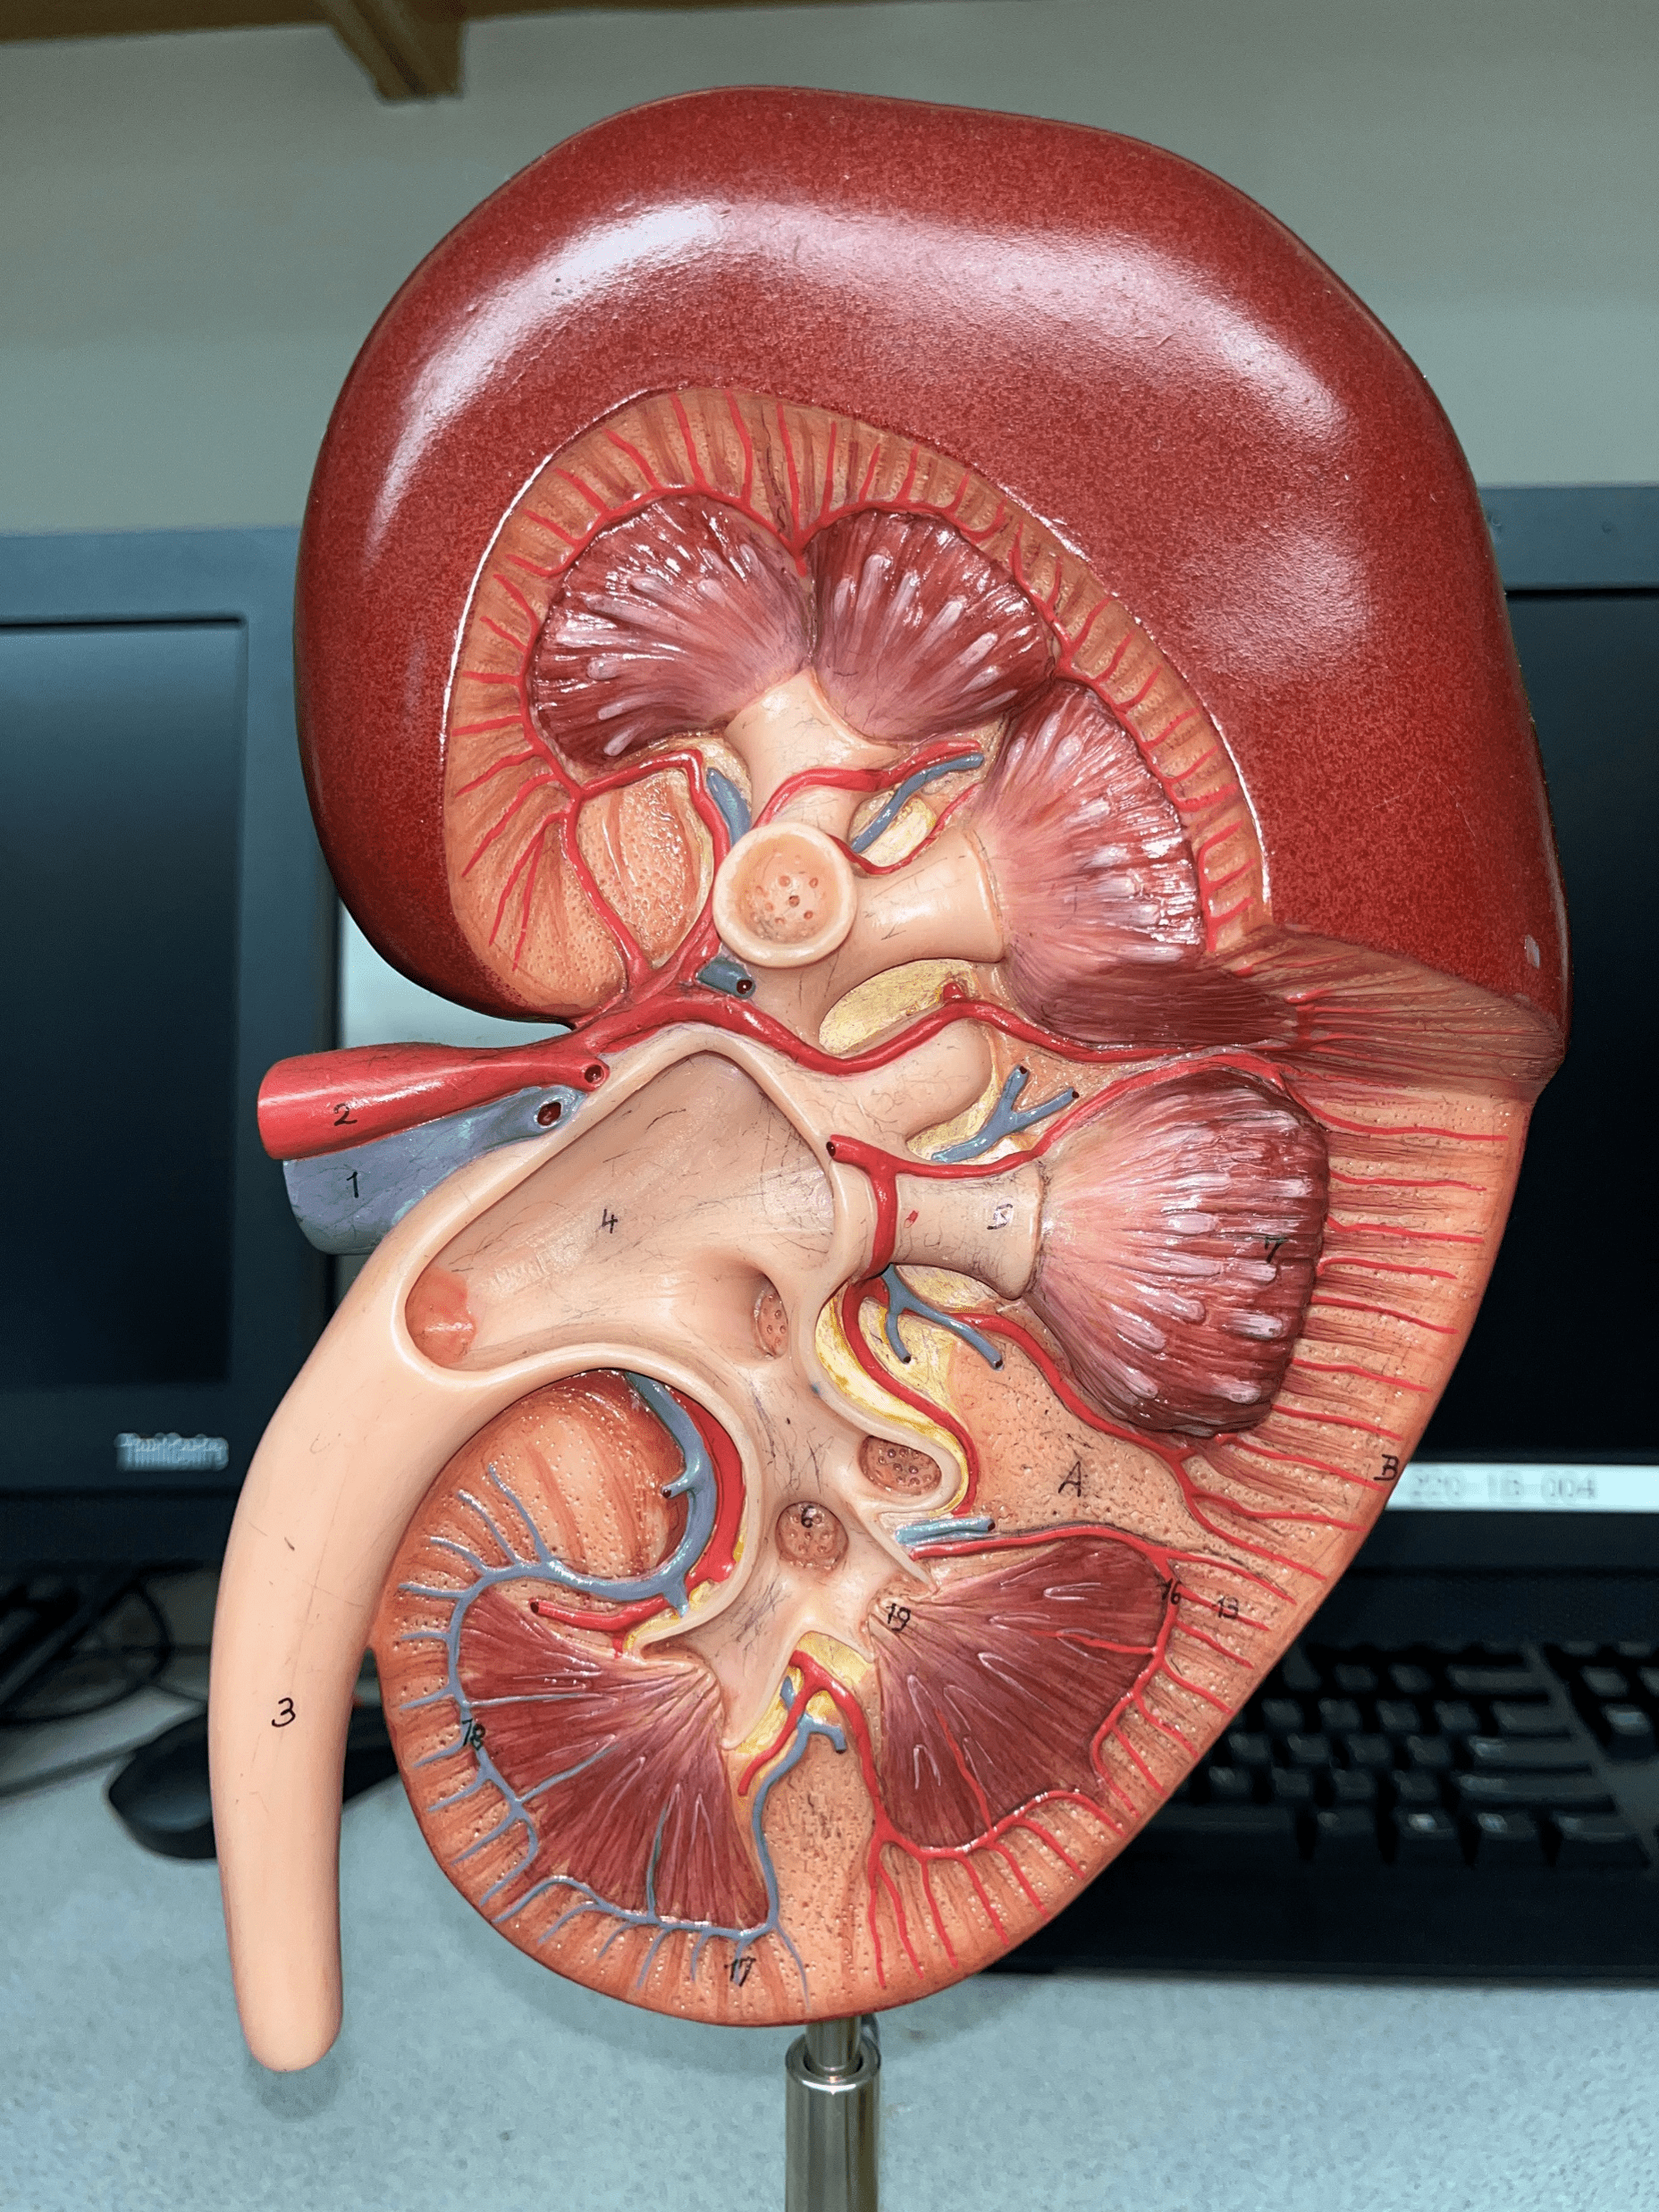

kidney

The organ that filters blood and excretes waste as urine.

renal capsule

The thin outer shell of the kidney.

renal hilum

• The concavity of the kidney.

• Admits the ureters, renal a., renal v., lymphatics, and nerves.

• Also known as the hilus of the kidney.

renal cortex

• The outermost region of the internal kidney.

• Superficial to the renal medulla.

• Appears slightly granular.

renal medulla

• The middlemost region of the internal kidney.

• Deep to the renal cortex and superficial to the renal pelvis.

• Contains triangular renal pyramids.

• Appears striated due to the presence of tubules and ducts.

renal pyramid

• A triangular structure found in the renal medulla.

• The base faces the renal cortex.

• The renal papilla (apex) faces the renal pelvis.

renal papilla

The apex of the renal pyramid facing the renal pelvis.

renal column

An area of granular tissue (similar to the cortex) between renal pyramids.

minor calyx

• A cup-like extension that collect urine from the renal papilla.

• Converges with others to form a larger major calyx.

major calyx

• The convergence of several minor calyces.

• Drains into the renal pelvis.

renal pelvis

• The innermost region of the internal kidney.

• Collects urine from the major calyces and drains it into the ureters.

• Includes the minor and major calyces.

renal artery

• The largest a. of the kidney.

• Supplies the entire kidney.

• Branches into smaller segmental aa.

renal vein

• The largest vein of the kidney.

• Drains blood from the entire kidney.

• The convergence of interlobar vv.

ureter

• A narrow tube channeling urine from the kidneys to the urinary bladder.